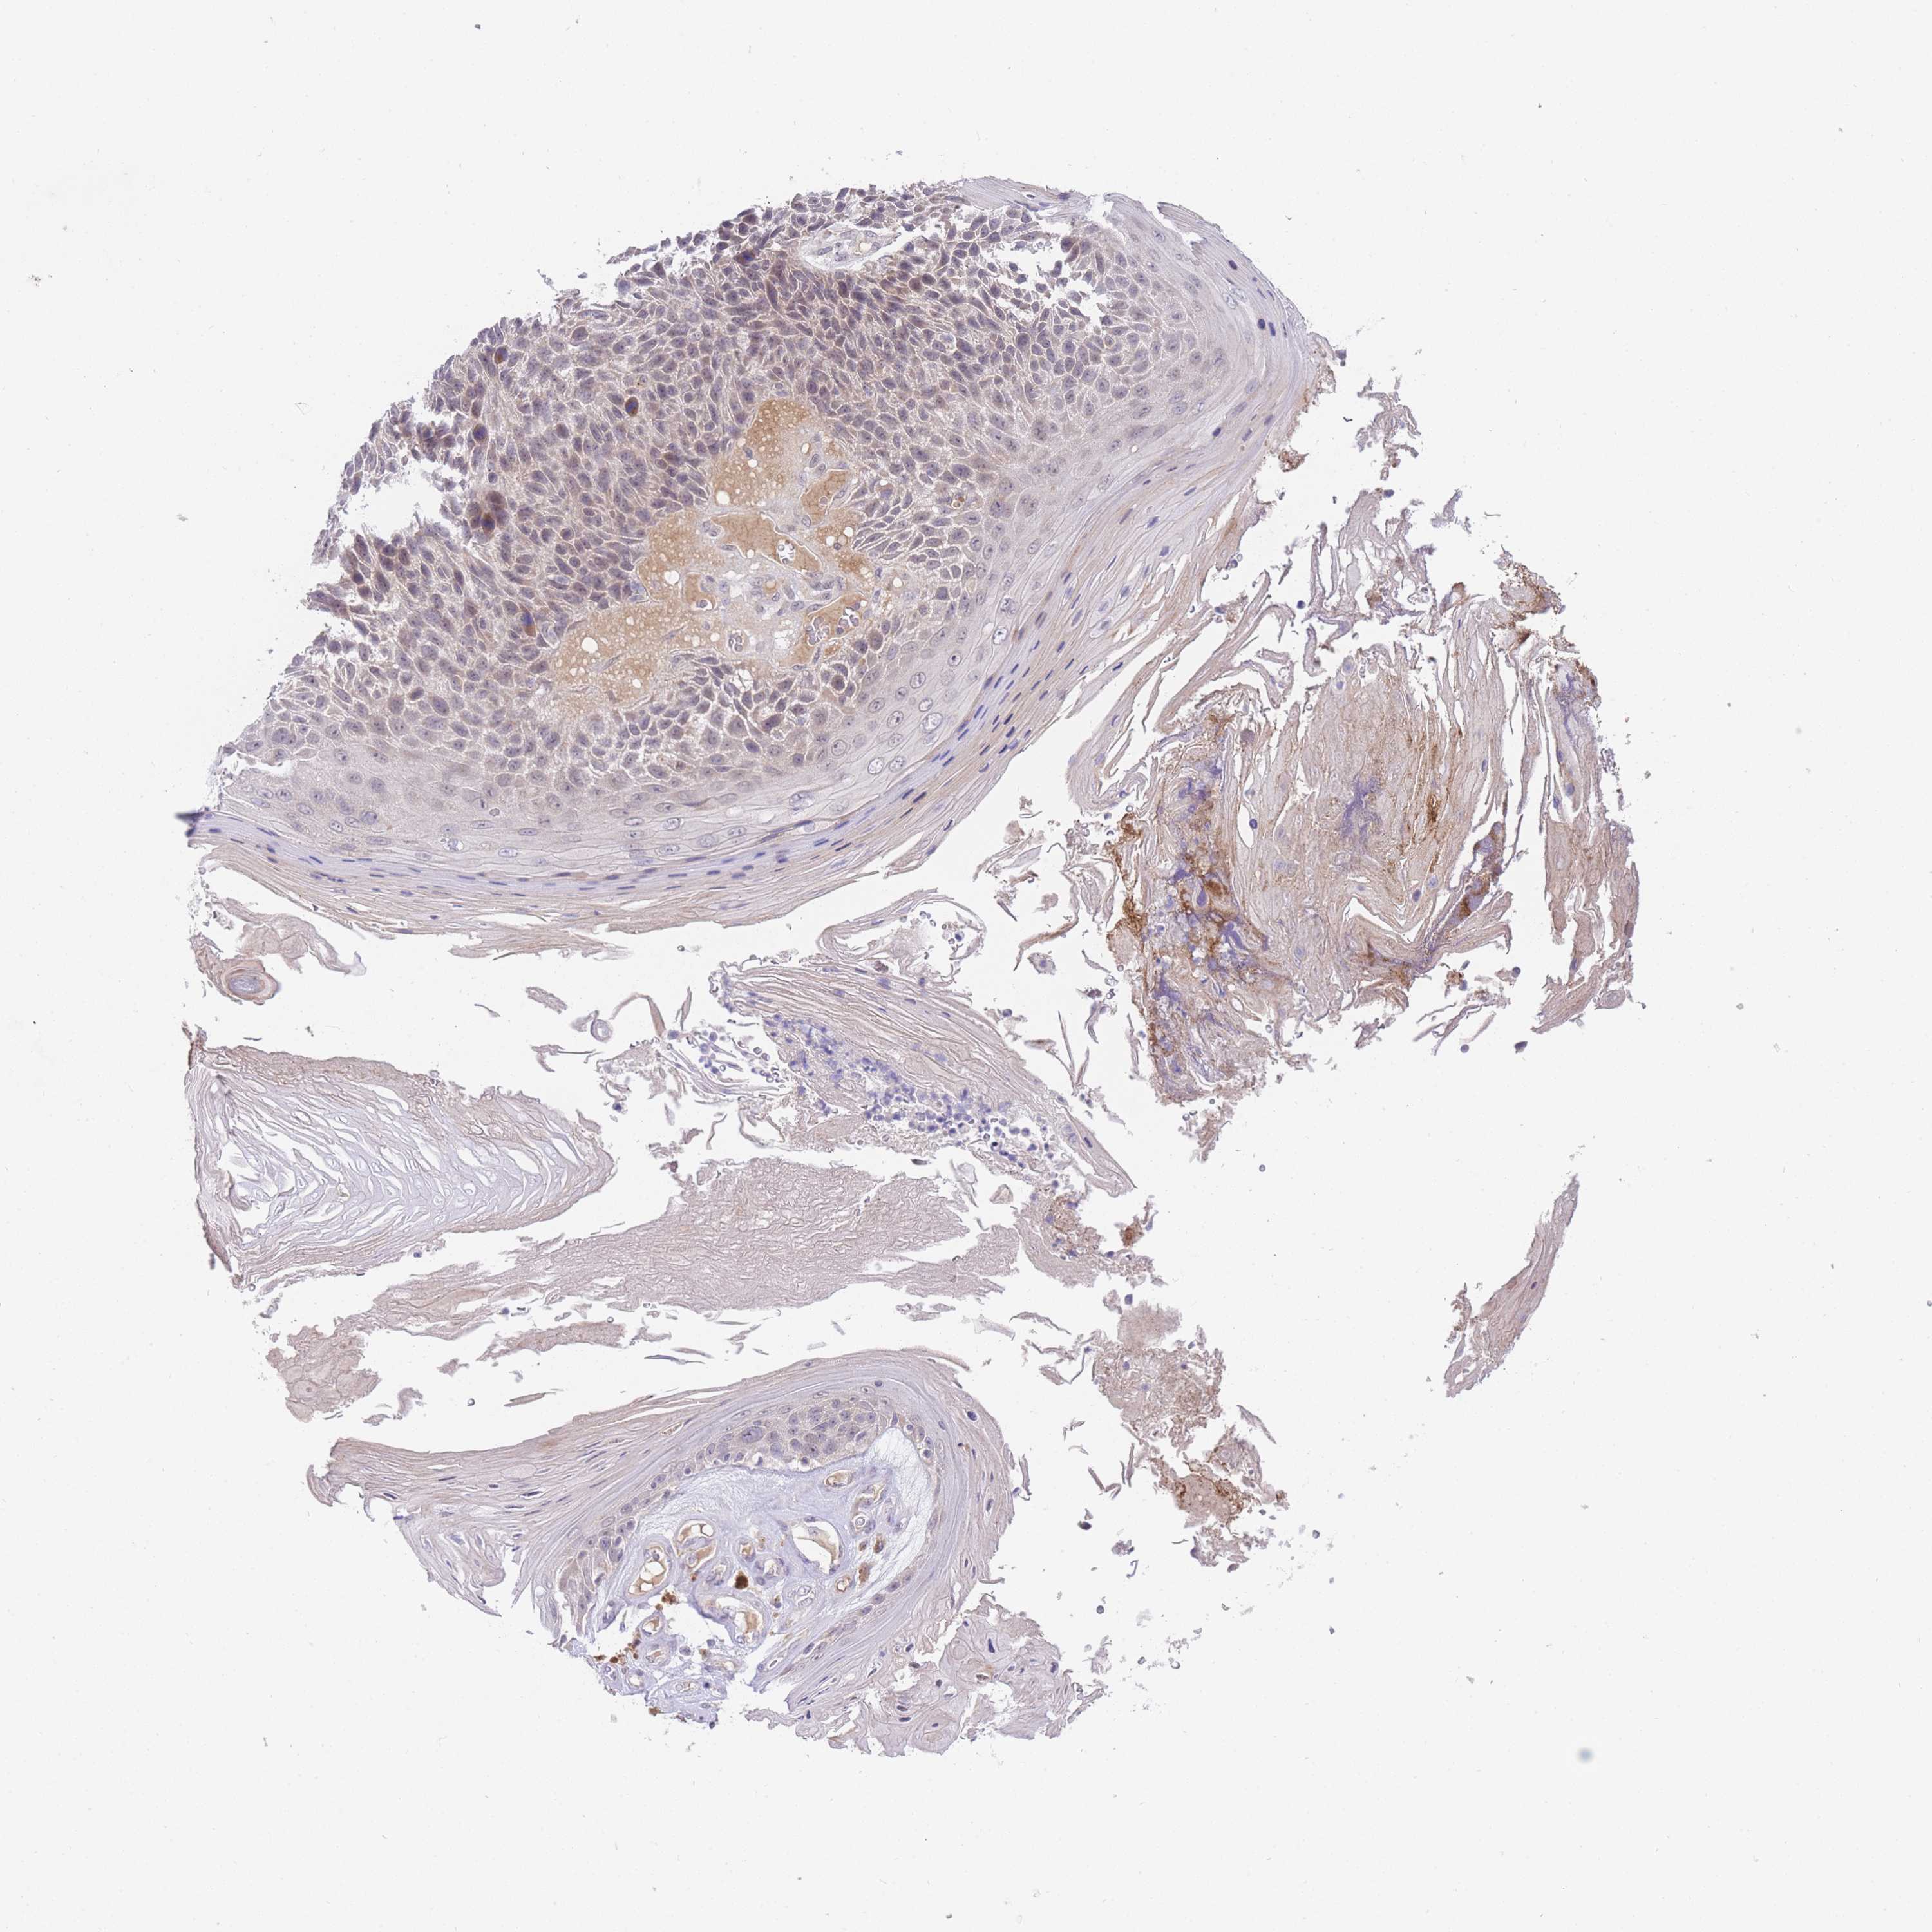

Basal cell and squamous cell cancer

SKIN CANCER - Protein expressioni

A mouse-over function shows sample information and annotation data. Click on an image to view it in a full screen mode. Samples can be filtered based on level of antibody staining by selecting one or several of the following categories: high, medium, low and not detected. The assay and annotation is described here.

Antibody stainingi

Antibody staining in the annotated cell types in the current human tissue is reported as not detected, low, medium, or high, based on conventional immunohistochemistry profiling in selected tissues. This score is based on the combination of the staining intensity and fraction of stained cells.

Each image is clickable and will lead to virtual microscopy that enables deeper exploration of all samples and also displays staining intensity scores, fraction scores and subcellular localization as well as patient and tissue information for each sample.

Antibody HPA049982

Staining

High

Medium

Low

Not detected

Intensity

Strong

Moderate

Weak

Negative

Quantity

>75%

75%-25%

<25%

None

Location

Nuclear

Cytoplasmic/membranous

Cytoplasmic/membranous,nuclear

Basal cell carcinoma

Squamous cell carcinoma, NOS

Squamous cell carcinoma, metastatic, NOS